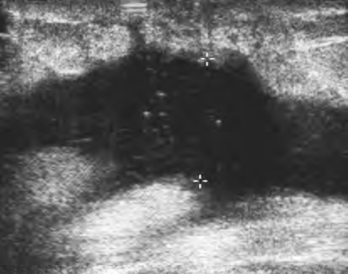

(3)若脓肿形成,可见不规则的液性暗区,密集光点反映了其黏稠,加压震动可见液体有波动感或见光点流动(图8-2),若破溃至体表,可见管道样低回声。

图8-2 乳腺脓肿声像图

乳腺组织内形成不规则的液区,黏稠不清晰